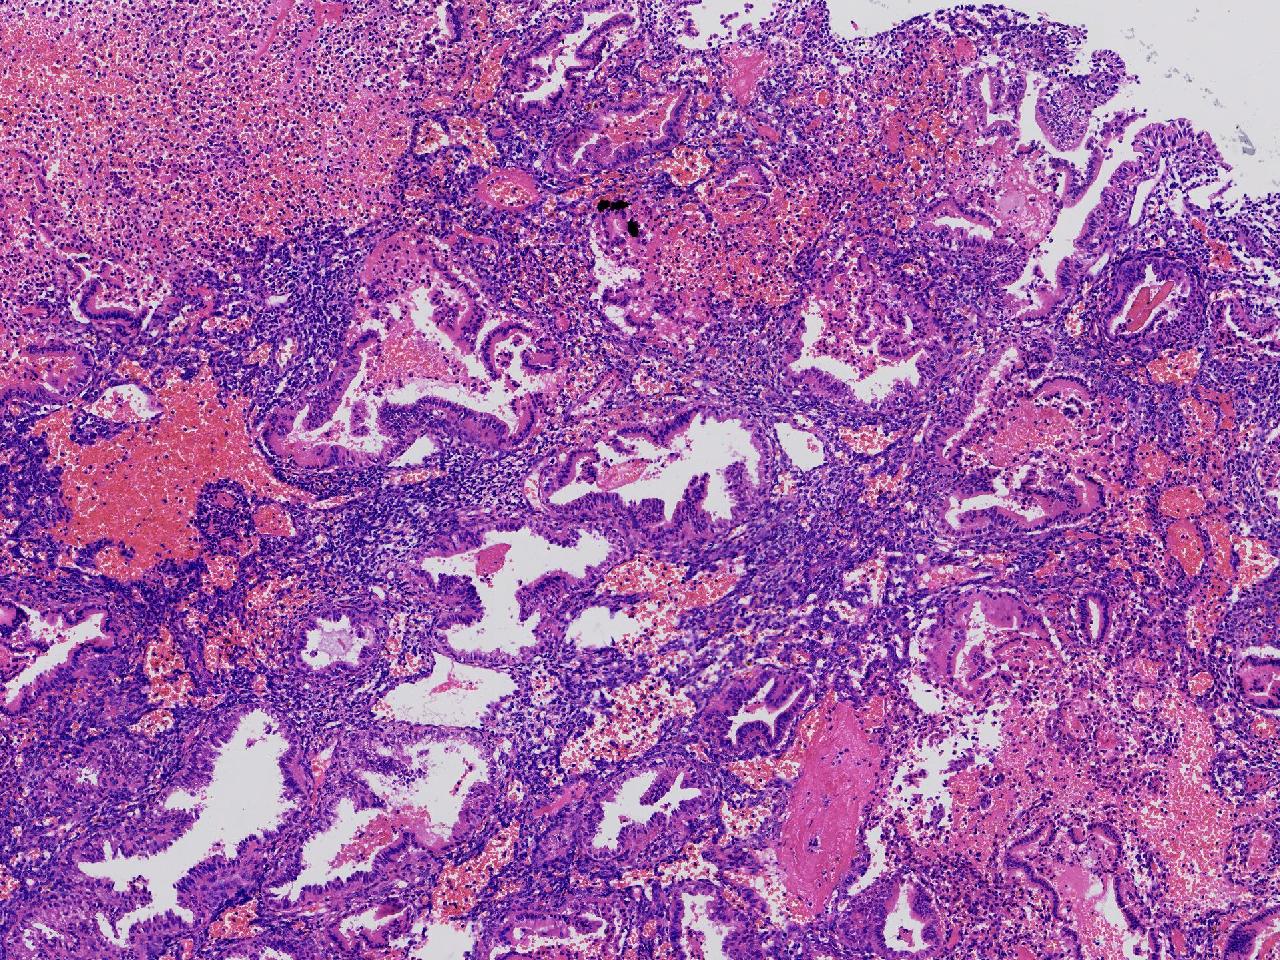

性别

女

年龄

45岁

临床诊断

阴道不规则出血20余天,

一般病史

彩超示:宫腔内见约41X11毫米的不均质回声区。宫腔镜示:宫腔形态正常,内膜粉红,不规则增厚。

标本名称

子宫内膜

大体所见

灰粉色不整形软组织多块,1.5X1X0.6厘米。

图1

分泌反应子宫内膜,伴有出血。

晚泌期及月经早期改变,局部呈啫酸性乳头状化生改变。